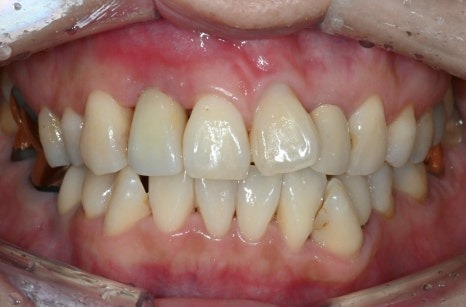

치료 전

수술 3주 후

수술 후 단 3주만에,

앞니 임플란트 보철물까지 장착하였고,

환자분은 어떠한 불편함도 없다고 하셨습니다.

단 3주의 기간에 임플란트 치료가

완료되길 원하시는 환자분의 기대를

단순히 과도하고 헛된 기대로 치부하지만은 않았습니다.